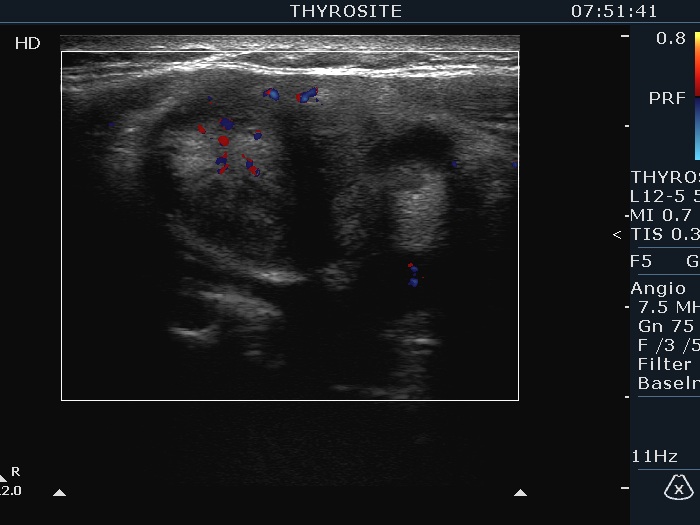

Ultrasonography. The thyroid was echonormal and had multiple nodules. The largest lesion in the right lobe was minimally hypoechoic had irregular borders and presented all three possible signs of an extrathyroidal spread. The vascularity was scanty. The largest nodule in the left lobe was also remarkable due to numerous echogenic lines and granules which were related to ventral cystic areas. So, these were back wall figures.